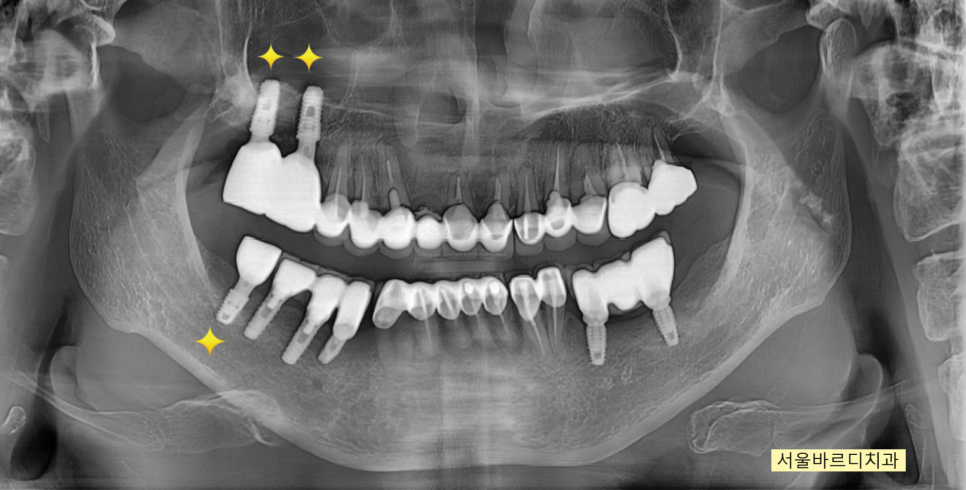

241127

완성된 모습입니다.

뼈가 부족한 윗니 어금니로 인해

시간이 조금 걸렸습니다.

240503

머리 부분은 하얀색으로

심미적이게 제작 완료!